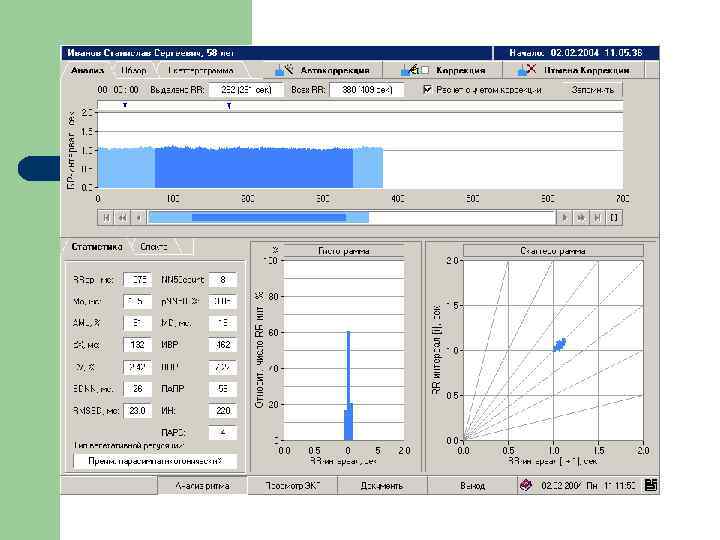

Ритмокардиография - один из методов регистрации ВСР. Ритмокардиограмма – графическое отображение последовательного временного ряда межсистолических интервалов в виде отрезков прямой линии, эквивалентных продолжительности пауз между сокращениями сердца.

Волновая структура РКГ RR (NN) мс 3 вида волн: “s”-волны или HF (high frequency) – 0, 15 -0, 4 Гц “m”-волны или LF (low frequency) – 0, 04 -0, 15 Гц “l”-волны или VLF (very low frequency) - 0, 003 -0, 04 Гц

Пример РКГ-комплекса